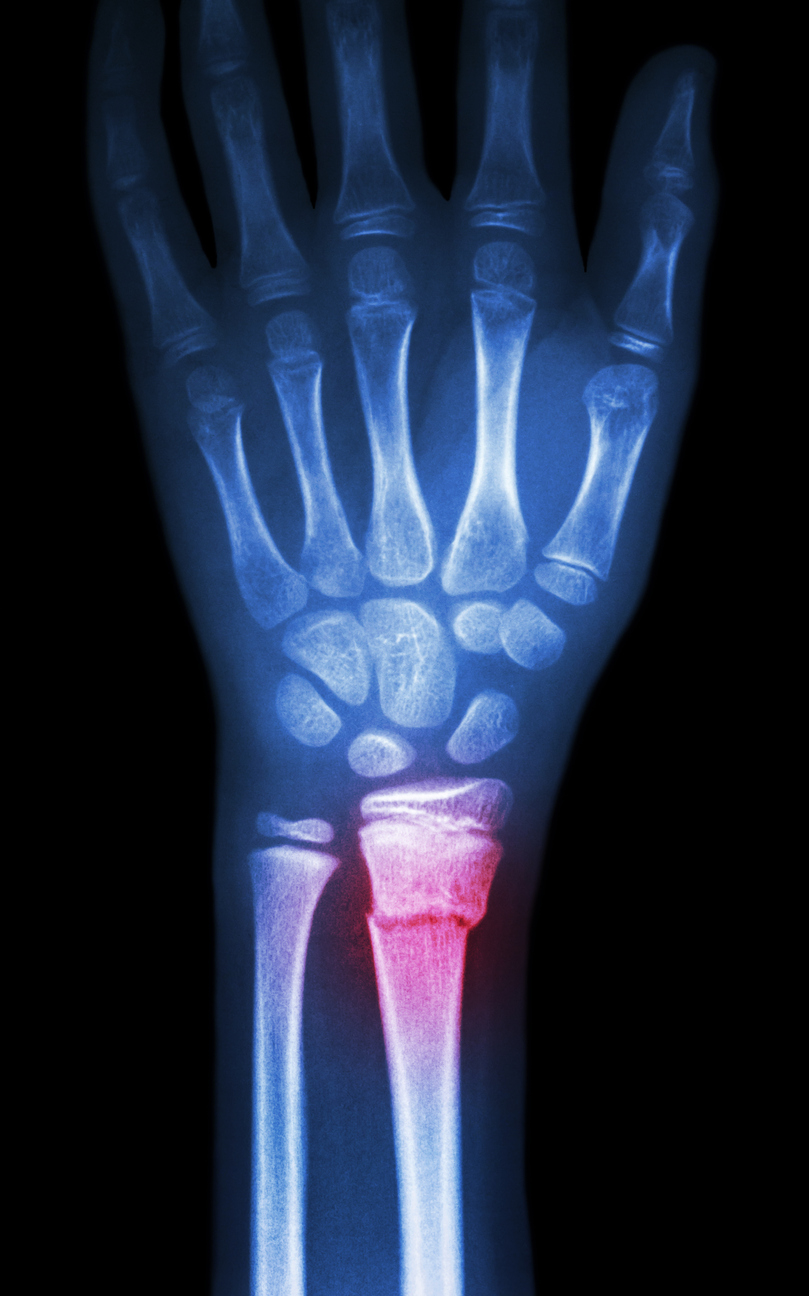

Treatable Common perinatal hand/wrist conditions surrounding pregnancy.

A woman’s body undergoes many changes to prepare and provide care for bringing a new child into the world. During these times surrounding pregnancy and the birth of a new child, a woman undergoes changes in hormonal balance, body fluid levels and weight. What many women don’t realize is that these natural dynamic processes contribute…